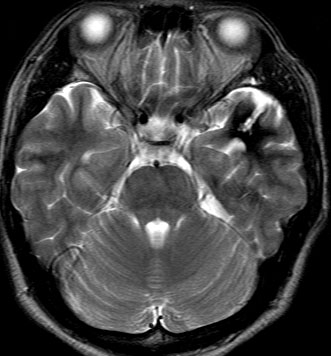

2度の延髄内出血を生じた海綿状血管腫です。でも初回の出血からすでに27年間がたちます。症状も回復して麻痺もなくていまは社会生活に困ることはありません。脳幹部の海綿状血管腫の中には1ヶ月に何回もひどい出血を繰り返すのもあるのですが,この例のように30年近い間に軽い出血が2回だけというのもあります。残念ながら正確にこれを予測することはできません。この患者さんの海綿状血管腫は手術で摘出すれば麻痺などの合併症の可能性があるのでしません。